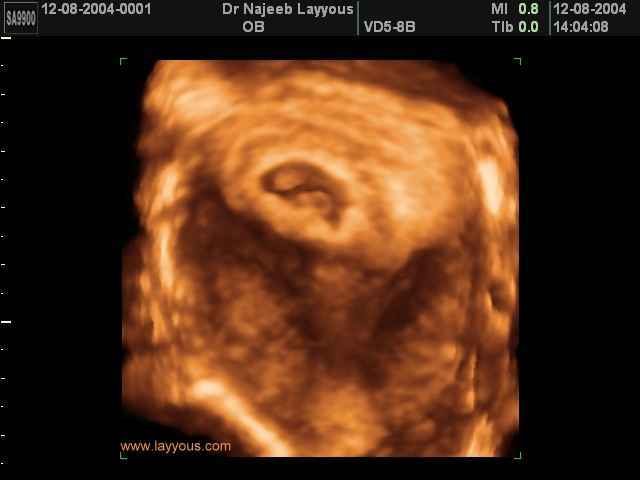

- 3D Photos Ecographie du Premier Trimestre

3D Photos Ecographie du Premier Trimestre (Photos d’échographie de tôt grossesse)| Dr N Layyous